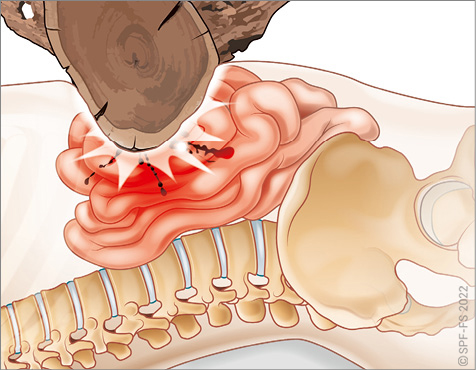

Le bassin

Le bassin osseux (ou pelvis) constitue la jonction entre la colonne vertébrale et les membres inférieurs. En forme d'entonnoir, plus large chez la femme que chez l'homme, il est composé par :